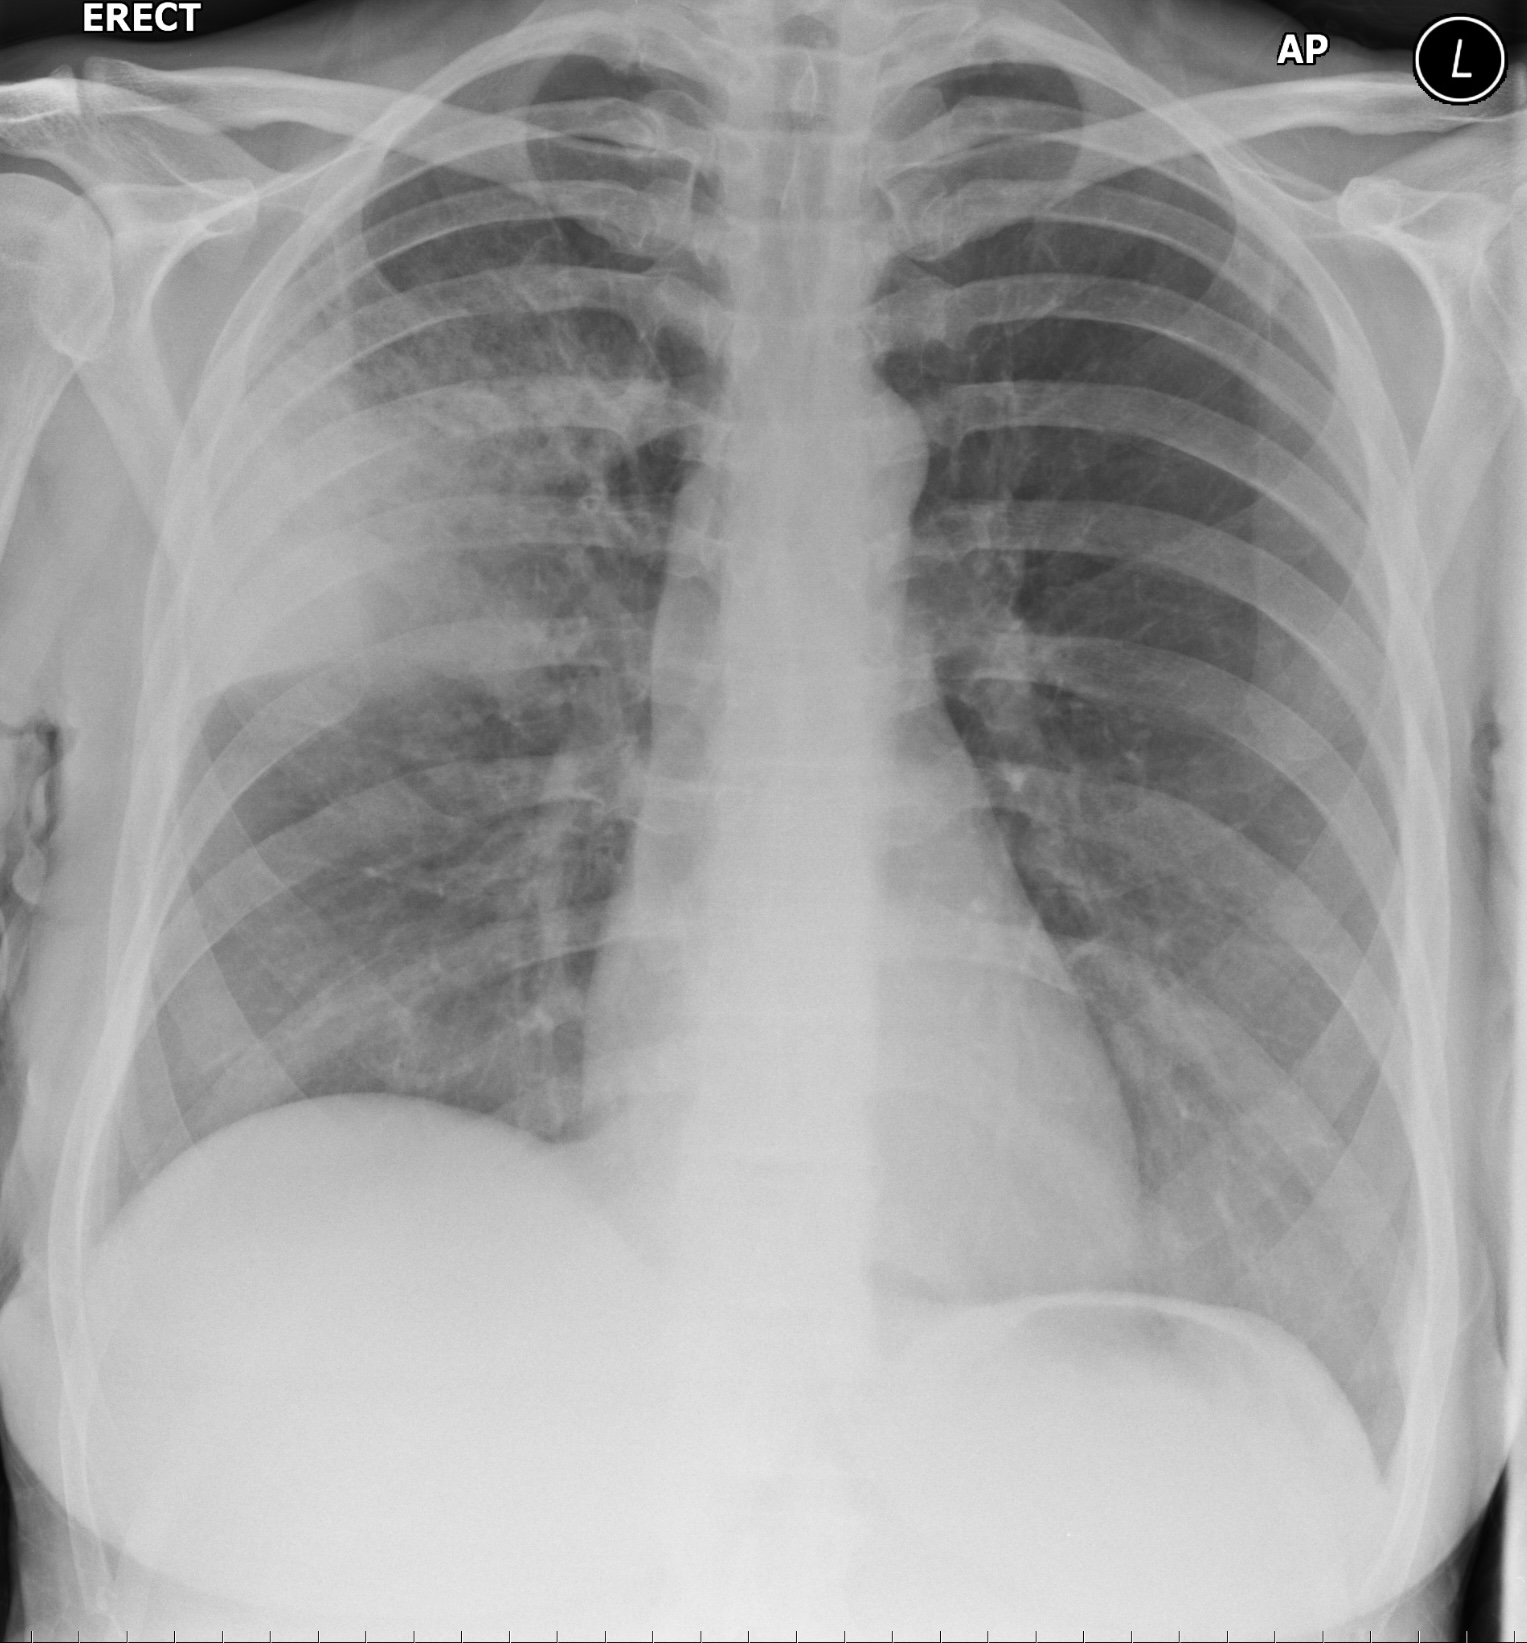

Right Upper Lobe Consolidation